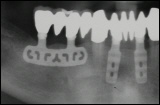

Diskimplantate

Diskimplantate sind scheibenförmige Implantate, die in der Horizontalen ausgedehnt sind. Sie hatten nach Angaben aus der Fachliteratur zumindest in der Vergangenheit wie die Blattimplantate dieselben Nachteile, eine hohe Bruchgefahr und eine schlechte Entfernbarkeit, die bei Entzündungen leider oftmals mit großen Knochenverlusten einherging.

Der Vorteil der Diskimplantate besteht nach Angaben des Herstellers in der Sofortbelastung durch die breitbasige Auflage, sowie der Einsatzmöglichkeit bei nur geringer Knochenhöhe.

Die leicht schräge Röntgenaufnahme (rechts) zeigt den Aufbau eines Diskimplantates.